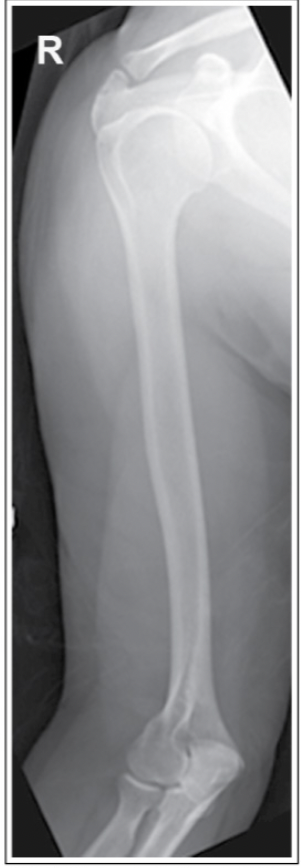

Which of the image criteria for an AP humerus is not met with this image?

a.The shoulder joint is not fully included

b.Humeral head in profile

c.Epicondyles are in profile

d.Exposure does not show bony details

A

What corrective action is necessary on the repeat image?

a.Arm should be internally rotated

b.CR should be angled caudad 15 degrees

c.Arm should be externally rotated

d.Arm should be abducted from the body